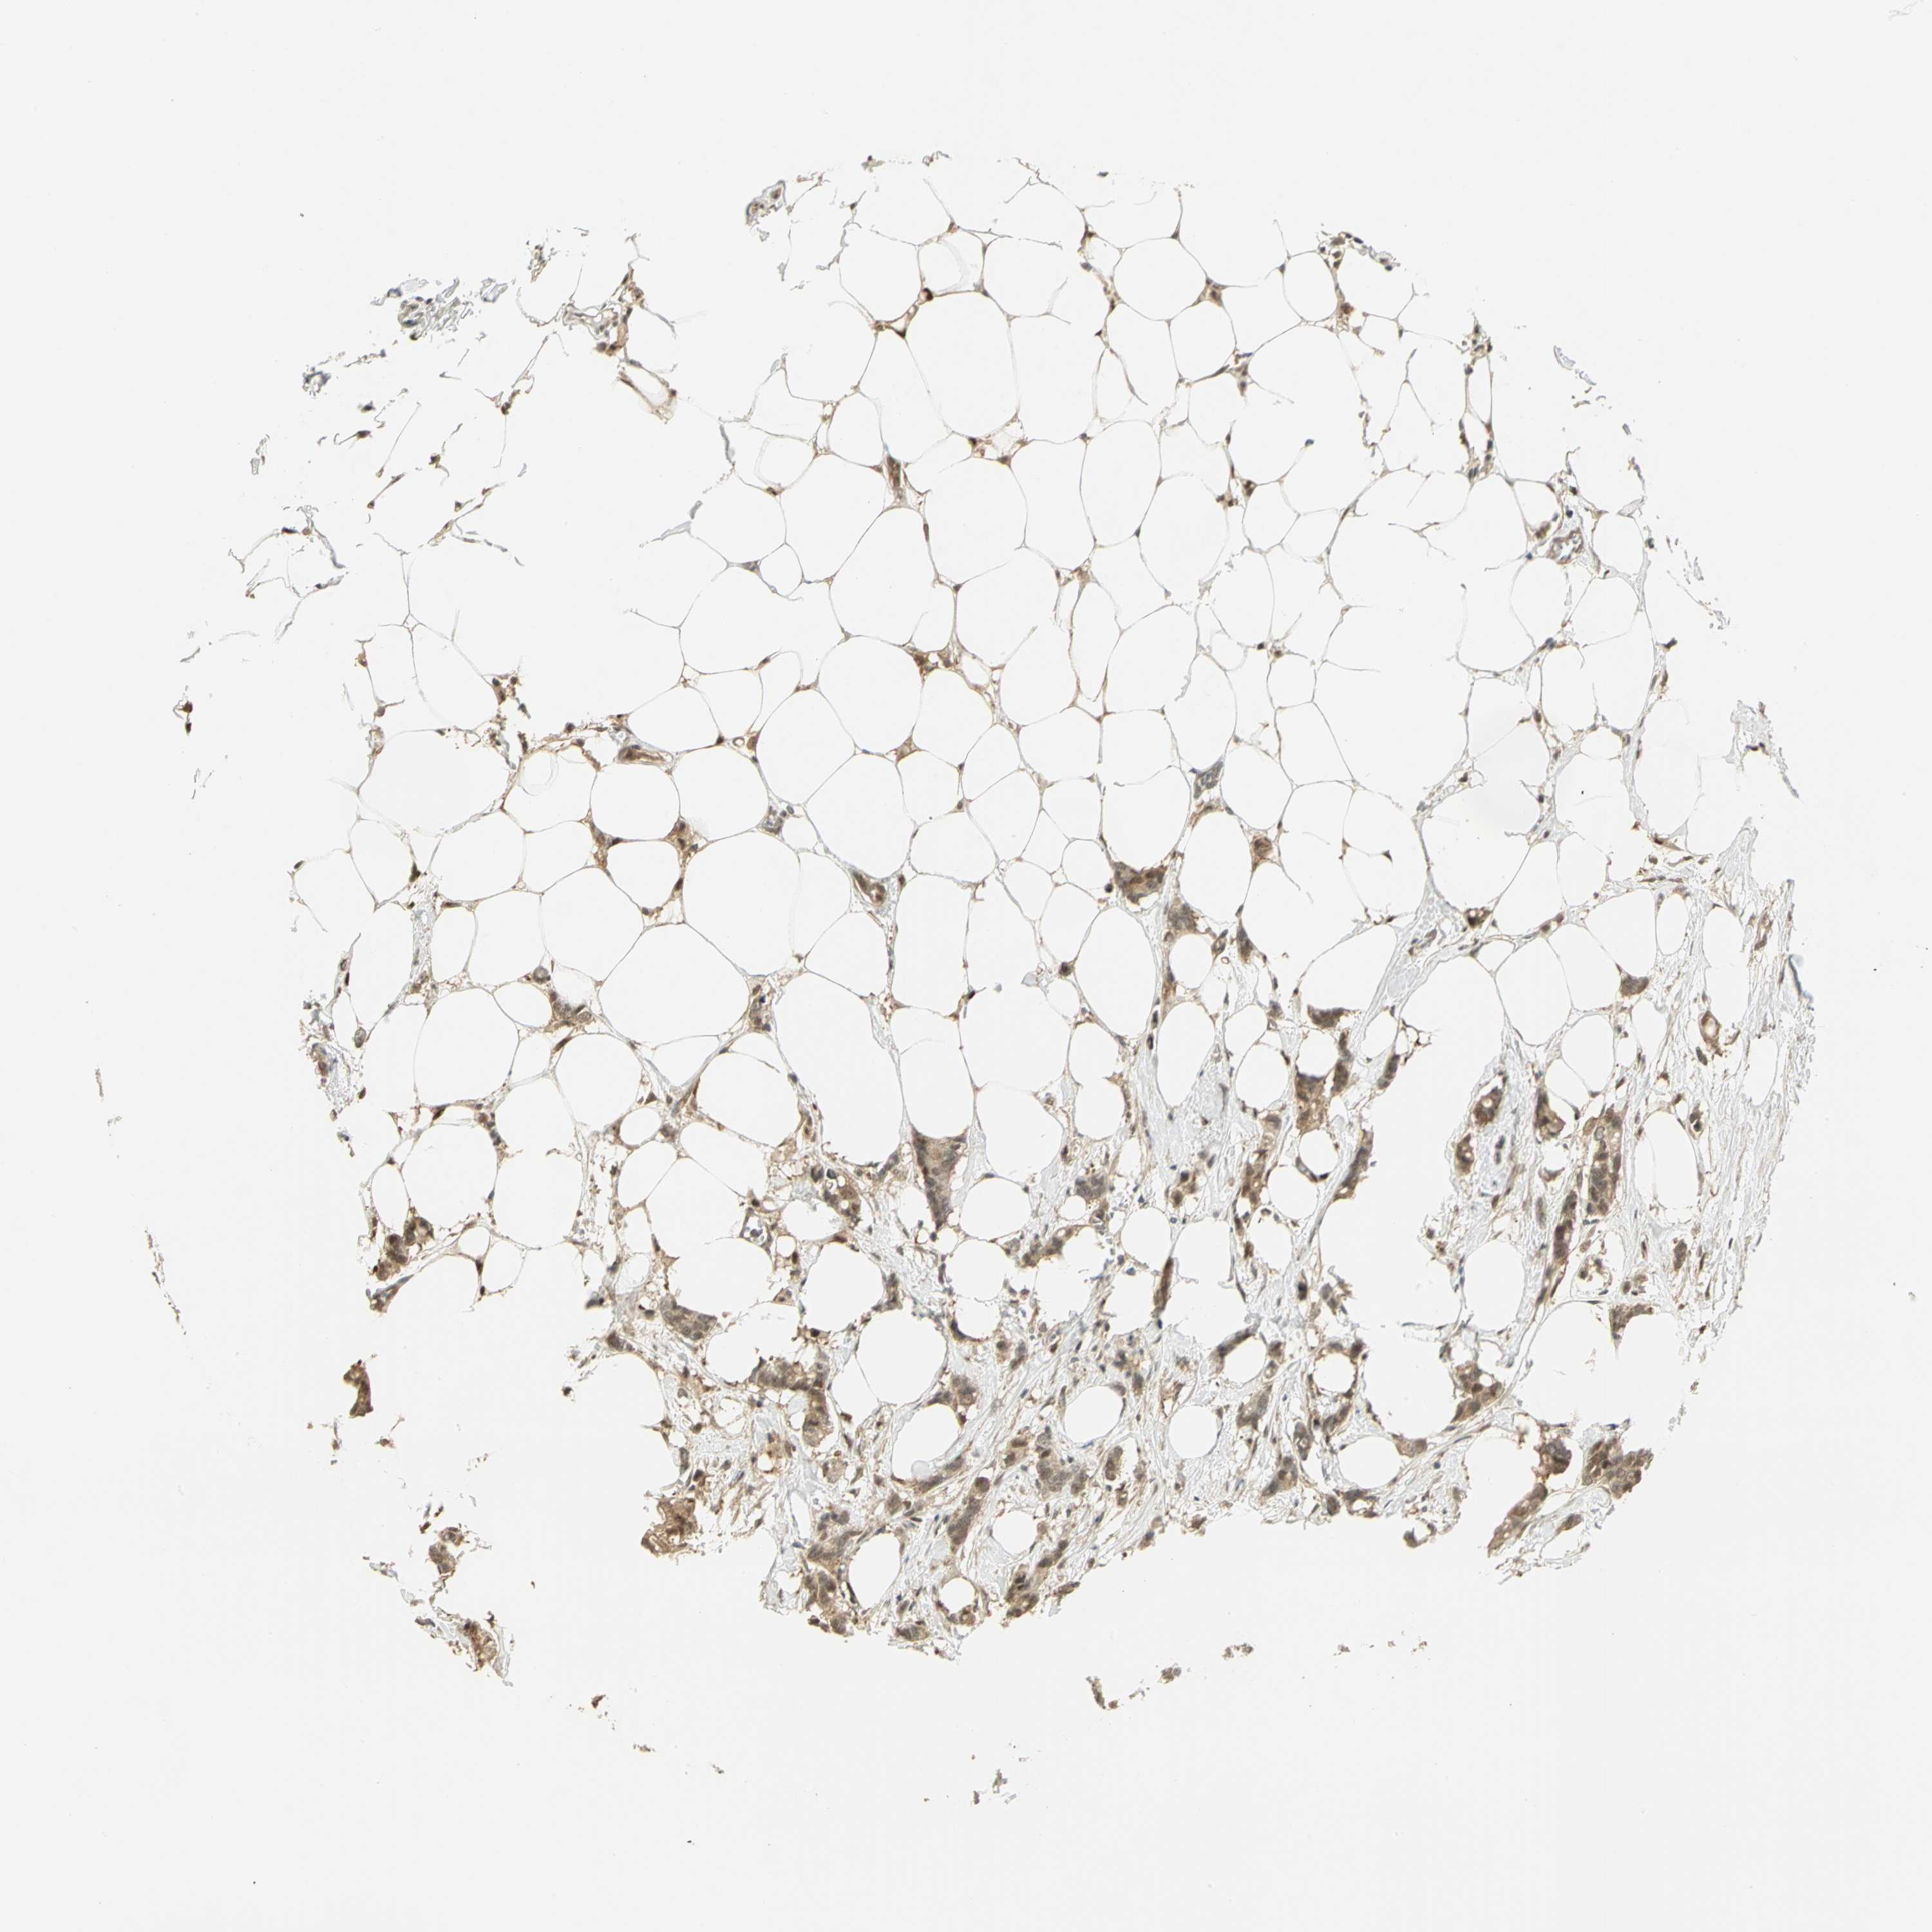

CANCER BREAST CANCER Show tissue menu

BRCA TCGA BRCA VALIDATION PROTEIN EXPRESSION